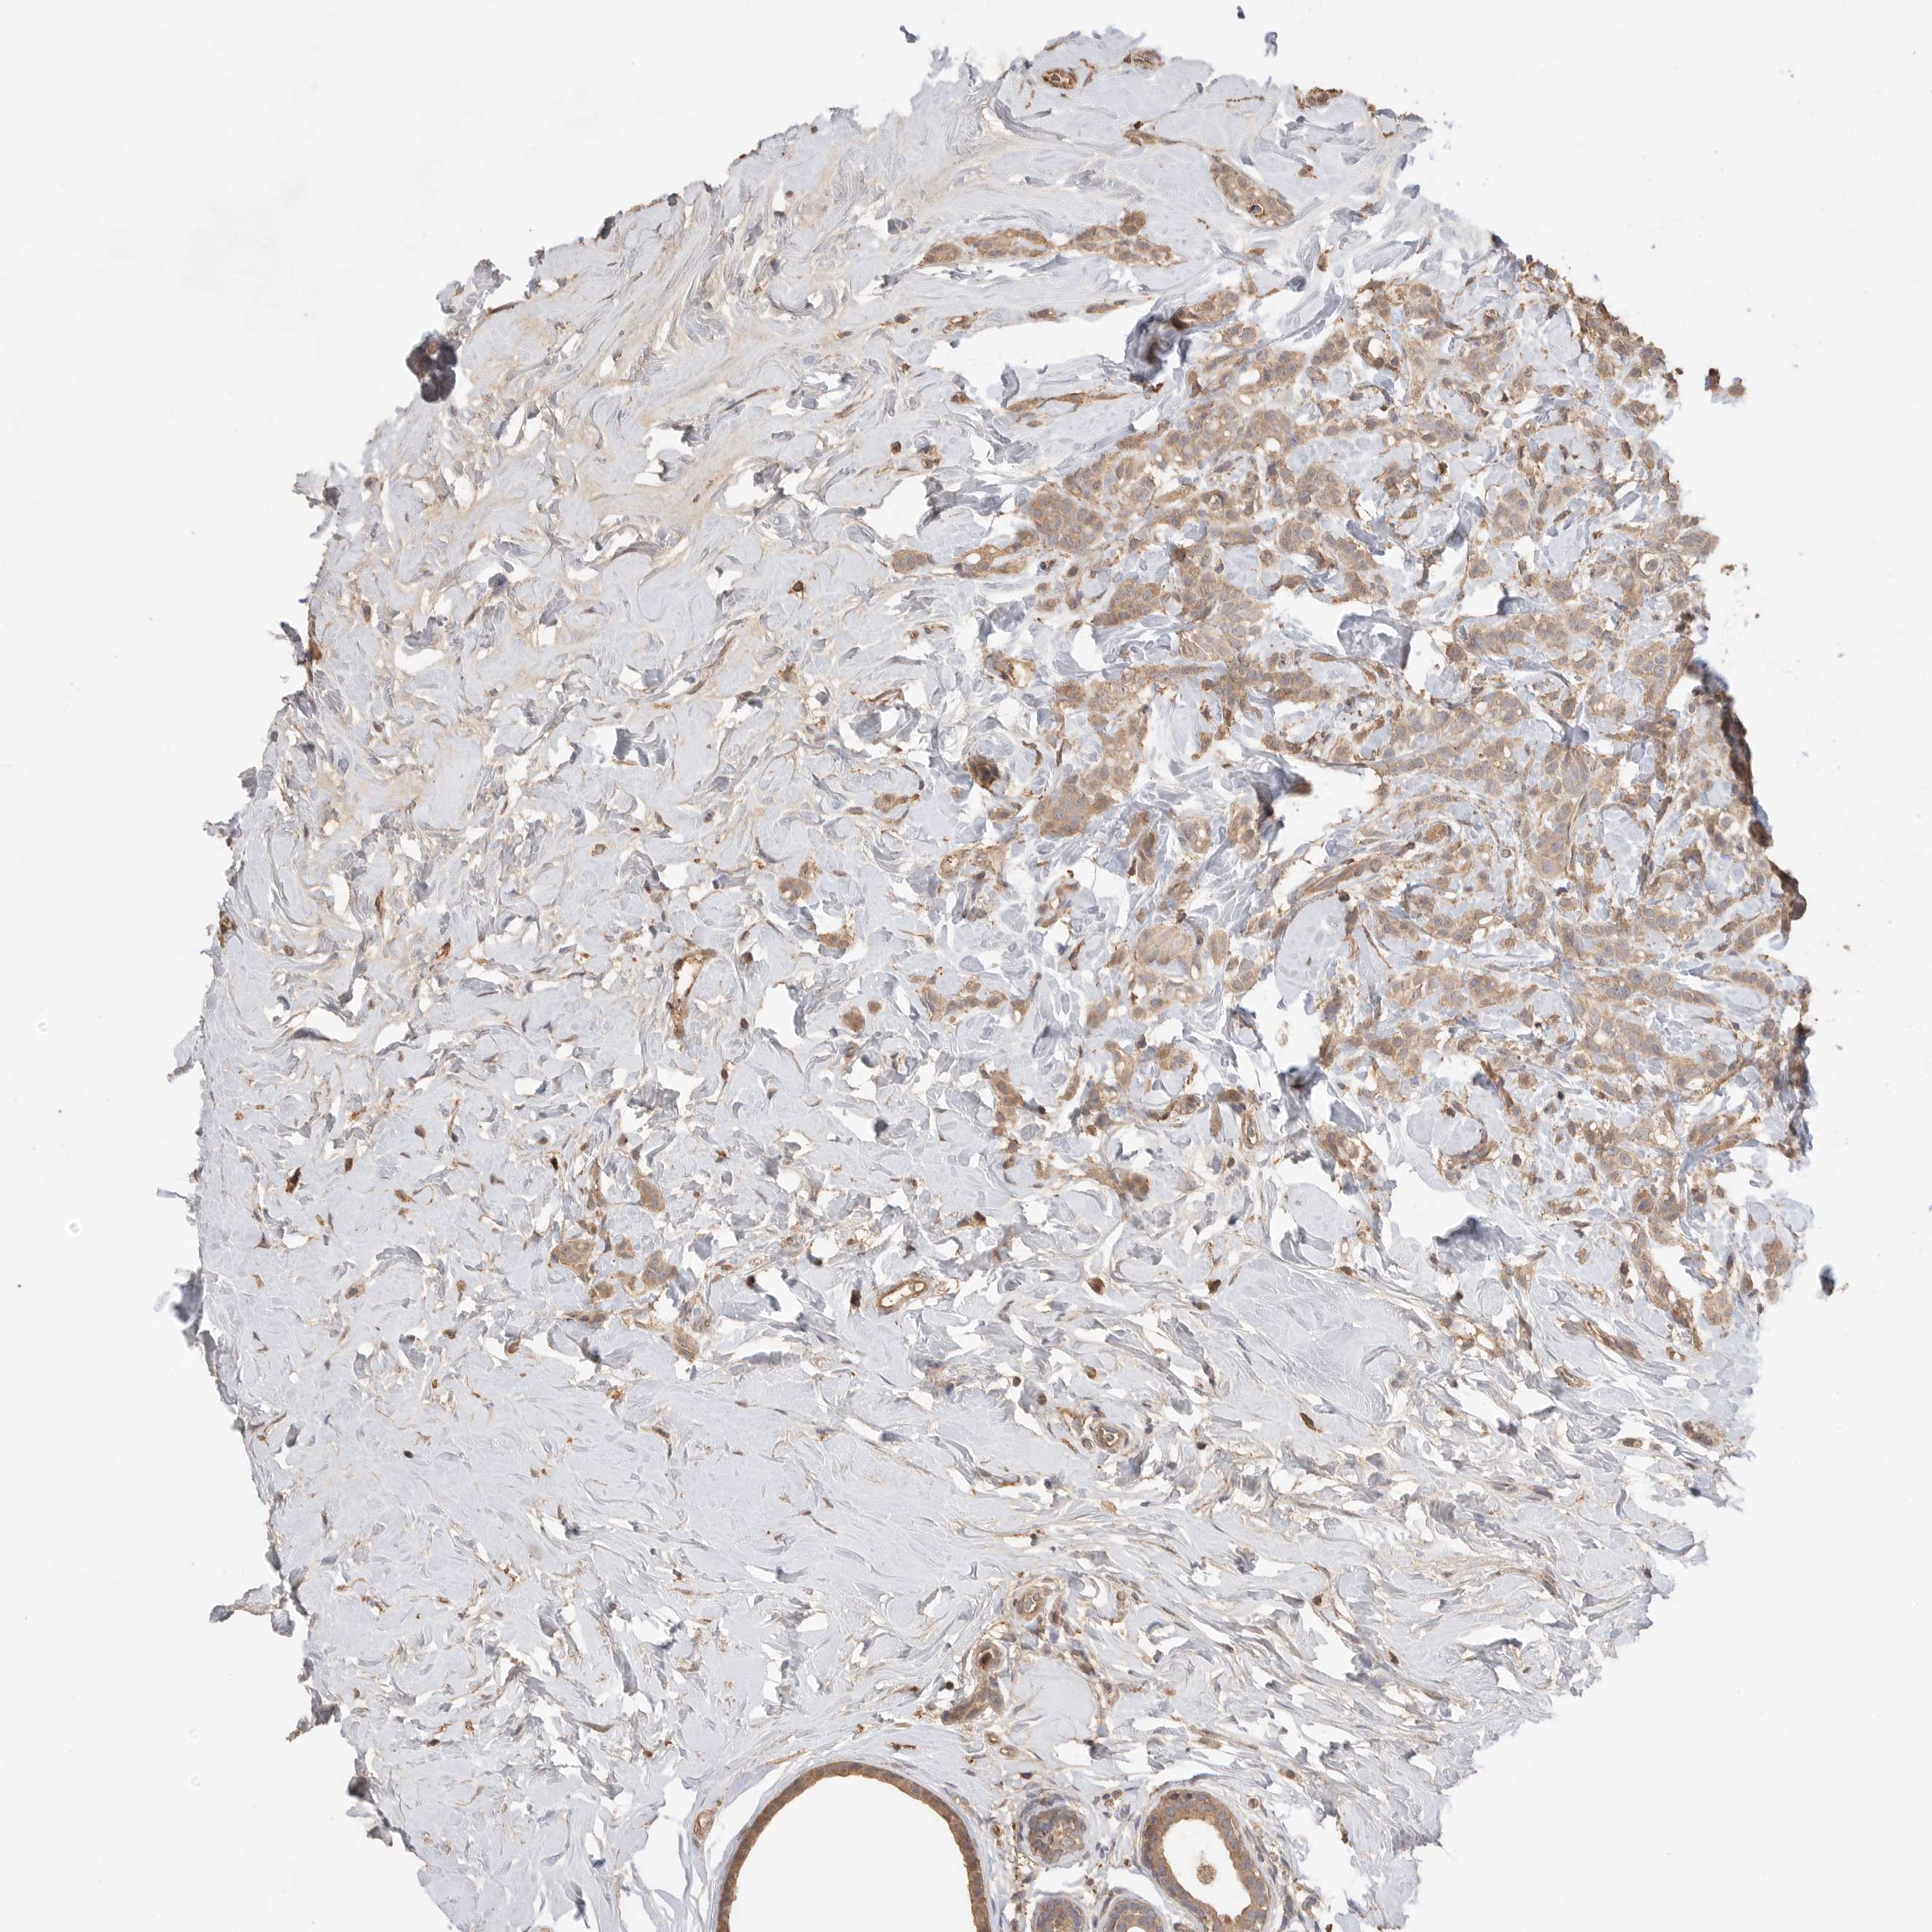

CANCER BREAST CANCER Show tissue menu

BRCA TCGA BRCA VALIDATION PROTEIN EXPRESSION

Breast cancer

Human cancer